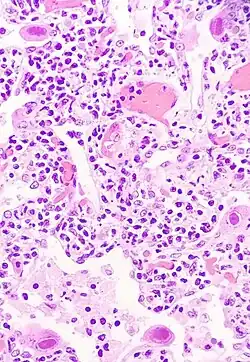

Pneumocytes infectés par le cytomégalovirus | ||||||||